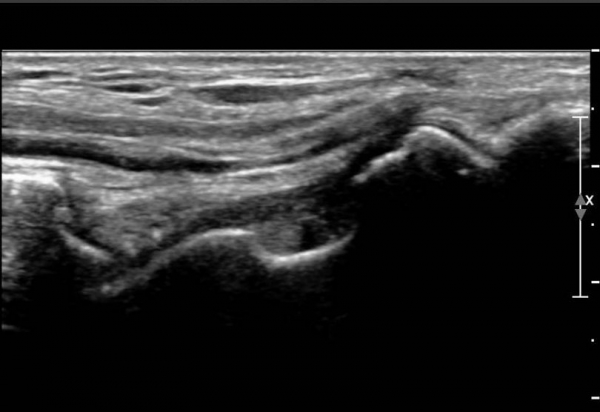

ÃÊÀ½ÆÄ ¼Ò°ß :  ¹ß¸ñ ¾Õ Á¾´Ü¸é°Ë»ç¿¡¼­ ¹ß¸ñ°üÀý³»  ¾à°£ÀÇ ¼ö¾×Àú·ù°¡ °üÂûµÊ(»çÁø 1).